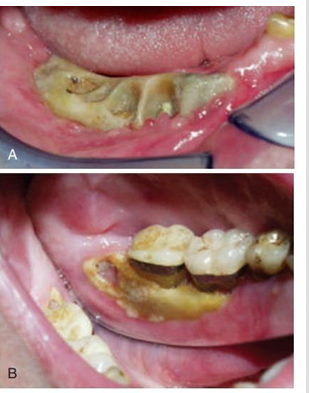

MFD EXAMS /23 6 1234567891011121314151617181920212223 You have 30 min to complete this exam. The timer will start once you begin Attention: Only a few minutes left! Please submit your answers soon. MFD 1 Get a quick sneak peek before the real exam !This trial quiz is designed to show you the question style, difficulty level, and how the options will appear on the platform. 1 / 23 1. What is the lethal dose and toxic dose of fluoride, management? Check 2 / 23 2. What the advantage of silver diamine over other methods and disadvantages ? Check 3 / 23 3. Method of topical fluoride application with concentration ? Check 4 / 23 4. What will happen if left untreated? Check 5 / 23 5. What changes that will happen if the habit stopped? Check 6 / 23 6. Give 3 of your initial stage of treatment? Check 7 / 23 7. What are the causes? Check 8 / 23 8. What is this? Check 9 / 23 9. Then they specified the type of pain and asked about the diagnosis Check 10 / 23 10. What other tests to check vitality of the pulp? Check 11 / 23 11. What are the factors will govern the Rx of Posterior cross bite ? Check 12 / 23 12. What are the factors that govern the treatment of anterior cross bite? Check 13 / 23 13. Name the appliance that you can use to treat this case? Check 14 / 23 14. Name 3 causes? Check 15 / 23 15. Name the most important clinical diagnostic information you need to know. (check RCSI intensive course )? Check 16 / 23 16. What do you see? Check 17 / 23 17. What is your treatment? Check 18 / 23 18. Name the investigations needed? Check 19 / 23 19. causes for gingival enlargement ? Check 20 / 23 20. What is the common side effect of this drug? Check 21 / 23 21. Name the drug that he may take to treat this condition? Check 22 / 23 22. The patient may have what? Check 23 / 23 23. What is this clinical condition? Check /31 2 12345678910111213141516171819202122232425262728293031 You have 30 min to complete this exam. The timer will start once you begin Attention: Only a few minutes left! Please submit your answers soon. MFD 2 Get a quick sneak peek before the real exam !This trial quiz is designed to show you the question style, difficulty level, and how the options will appear on the platform. 1 / 31 1. Mention 2 fixed space maintainers and 2 removable space maintainers other from mentioned : Check 2 / 31 2. Other space maintenance used for child lost primary second molar E before the eruption of the permanent molars ? Check 3 / 31 3. What are the difference between nance appliance and Transpalatal arch Check 4 / 31 4. What material used to attach band? Check 5 / 31 5. What instruction you give to patient? Check 6 / 31 6. Name other fixed space maintainer used in upper jaw and mechanism of their action? Check 7 / 31 7. What component of this appliance? Check 8 / 31 8. What is this appliance , for what its used ? Check 9 / 31 9. Treatment? Check 10 / 31 10. Define Abrasion and Erosion? Check 11 / 31 11. What does this picture show? Check 12 / 31 12. what investigations you can do ? Check 13 / 31 13. Drugs can lead to lichenoid reaction Check 14 / 31 14. What extra oral features in “ Lichenoid reaction )? Check 15 / 31 15. What microscopical features of it ( licheonoid reaction )? Check 16 / 31 16. Definitive diagnosis ? Check 17 / 31 17. Mention type of suggested biopsy ? Check 18 / 31 18. Mention 4 differential diagnosis ? Check 19 / 31 19. Mention 4 questions you will ask the patient ? Check 20 / 31 20. Give 4 intraoral decription of what you see ? Check 21 / 31 21. What the other surgery can be performed to make prothesis? Check 22 / 31 22. Can this tooth stand with fixed prothesis? (in the opg )à taken from Malek file ? Check 23 / 31 23. Radiograph of missing multiple teeth consider it according to Antes law? ON which tooth you will make Abutment ? Check 24 / 31 24. What is Antes law? Check 25 / 31 25. What is best one to use as abutment in fixed prosthesis A or B? Check 26 / 31 26. What relevance of this picture? Check 27 / 31 27. What’s complication of doing surgery in this area floor of mouth? Check 28 / 31 28. Other 2 radiograph needed in diagnosis? Check 29 / 31 29. Give 4 differential diagnosis? Check 30 / 31 30. What can you see ? Check 31 / 31 31. What is the name of radiograph? Check Your score is /30 1 123456789101112131415161718192021222324252627282930 You have 30 min to complete this exam. The timer will start once you begin Attention: Only a few minutes left! Please submit your answers soon. MFD 3 Get a quick sneak peek before the real exam !This trial quiz is designed to show you the question style, difficulty level, and how the options will appear on the platform. 1 / 30 1. Treatment? Check 2 / 30 2. Histopathology? Check 3 / 30 3. Differential diagnosis Check 4 / 30 4. Clinical features’? Check 5 / 30 5. Patient said, this lesion is very frequent, why? Check 6 / 30 6. What are the causes for ulcers? Check 7 / 30 7. Patient have other signs like uveitis ,Genital ulcerations which syndrome he had ? Check 8 / 30 8. Name of the lesion ? Check 9 / 30 9. Mention some TMJ movement ? Check 10 / 30 10. Blood supply ? Check 11 / 30 11. Nerve supply ? Check 12 / 30 12. Which muscles close? Check 13 / 30 13. Action of open and open wide? Check 14 / 30 14. Why it’s Atypical joint ? Check 15 / 30 15. Name of the ligaments ? Check 16 / 30 16. What would be your management? Check 17 / 30 17. Bacteria involved Check 18 / 30 18. Which type of Periodontitis? Check 19 / 30 19. Treatment? Check 20 / 30 20. Histopathology? Check 21 / 30 21. Differential diagnosis? Check 22 / 30 22. Clinical features? Check 23 / 30 23. What are the time frames for making a complaint? Check 24 / 30 24. What are the 3 points related to negligence? Check 25 / 30 25. Who is allowed access to the patient records? Check 26 / 30 26. How to differentiate if it is upper or lower motor neuron lesion? Check 27 / 30 27. Management? Check 28 / 30 28. What are the causes? Check 29 / 30 29. What should you advise the patient to do? Check 30 / 30 30. What is this lesion? Check Your score is /24 1 123456789101112131415161718192021222324 You have 30 min to complete this exam. The timer will start once you begin Attention: Only a few minutes left! Please submit your answers soon. MFD 4 Get a quick sneak peek before the real exam !This trial quiz is designed to show you the question style, difficulty level, and how the options will appear on the platform. 1 / 24 1. What does MRONJ stands for? Check 2 / 24 2. Give definition for MRONJ Check 3 / 24 3. For what medical problems these medications are used? Check 4 / 24 4. Stages of MRONJ 3 Check 5 / 24 5. What’s this appliance? Check 6 / 24 6. At what age is it used? Check 7 / 24 7. What type of malocclusion is it used to treat? Check 8 / 24 8. What changes will produce? (4 options) Check 9 / 24 9. Disadvantages? Check 10 / 24 10. Why is it flabby tissue? Check 11 / 24 11. what is this condition called? Check 12 / 24 12. Causes ? Check 13 / 24 13. Clinical Features ? Check 14 / 24 14. How to avoid it ? Check 15 / 24 15. Management? Check 16 / 24 16. Ideal post length and width Check 17 / 24 17. Definition of Ferrule it’s the Check 18 / 24 18. What is the importance of the ferrule effect ? Check 19 / 24 19. Describe the radiolucency? Check 20 / 24 20. Give 6 differential diagnosis? Check 21 / 24 21. Give 5 radiographical features? Check 22 / 24 22. What is the difference between incisional and excisional biopsy? Check 23 / 24 23. What other 2 plain radiographs we can we can take? Check 24 / 24 24. ALARA? Check Your score is /22 1 12345678910111213141516171819202122 You have 30 min to complete this exam. The timer will start once you begin Attention: Only a few minutes left! Please submit your answers soon. MFD 5 Get a quick sneak peek before the real exam !This trial quiz is designed to show you the question style, difficulty level, and how the options will appear on the platform. 1 / 22 1. . Types of external root resorption? Check 2 / 22 2. The cause of root resorption in the pic? Check 3 / 22 3. How you will treat it? Check 4 / 22 4. What is this probe? Check 5 / 22 5. What is the mark a ? Check 6 / 22 6. What is the mark b ? Check 7 / 22 7. What is the score from the given reading? Check 8 / 22 8. What is the treatment need of the patient according to the score? Check 9 / 22 9. What is the differential diagnosis ? Check 10 / 22 10. Four clinical features of the lesion? Check 11 / 22 11. Treatment ? Check 12 / 22 12. Describe what do you see? Check 13 / 22 13. Causes for it ? Check 14 / 22 14. Treatment ? Check 15 / 22 15. Picture of patient with Anaphylaxis…after taking Check 16 / 22 16. What is diagnosis? - Check 17 / 22 17. What a the signs of Anaphyalxis reactions ? Check 18 / 22 18. What first line of treatment? Dose? Route of Adminstration? Check 19 / 22 19. Other drug used? Check 20 / 22 20. What are expected complications if not treated ? Check 21 / 22 21. What precautions should be made to prevent anaphylaxis reaction ? - Check 22 / 22 22. Name 10 drug in emergency used with their route of Administration and their condition they use in? Check Your score is /36 1 123456789101112131415161718192021222324252627282930313233343536 You have 30 min to complete this exam. The timer will start once you begin Attention: Only a few minutes left! Please submit your answers soon. MFD 6 Get a quick sneak peek before the real exam !This trial quiz is designed to show you the question style, difficulty level, and how the options will appear on the platform. 1 / 36 1. . What are cases that you have to extract the primary tooth? Check 2 / 36 2. D. What are the indications for extraction? Check 3 / 36 3. What are your treatment options? Check 4 / 36 4. Investigations? Check 5 / 36 5. Type of trauma? Check 6 / 36 6. Patient diagnosed with sjorgen syndrome Histology ? - Check 7 / 36 7. Patient diagnosed with sjorgen syndrome Mention four blood investigations ? Check 8 / 36 8. Patient diagnosed with sjorgen syndrome Mention two sites where can we take the biopsy Check 9 / 36 9. Patient diagnosed with sjorgen syndrome How can you differentiate between primary and secondary ? Check 10 / 36 10. Gingival inflammation present in which syndrome Check 11 / 36 11. What is the treatment? Check 12 / 36 12. mention another connective tissue disease that can lead to lesions “ intraorally “ similar to the Lichen planus ? Check 13 / 36 13. what serious complication can arise from Erosive lichen planus ? Check 14 / 36 14. If it was atrophic lesion what histology might be seen ? Check 15 / 36 15. List the histological features of lichen planus ? Check 16 / 36 16. Lichen planus what dose it affect? Check 17 / 36 17. Age group commonly affected ? -ref SAQ Check 18 / 36 18. What are the clinical presentation ‘ types of lichen planus ‘ Check 19 / 36 19. What might you see in patient’s body that has a relation to this lesion? Check 20 / 36 20. What are the differential diagnoses? Check 21 / 36 21. Factors for platelet adhesion? Check 22 / 36 22. What can you see? Check 23 / 36 23. Other 2 process of hemostasis? Check 24 / 36 24. Two diseases in which they increase ? Check 25 / 36 25. Two diseases in which they decrease? Check 26 / 36 26. Medical term when they decrease? And if they increased Check 27 / 36 27. Function Check 28 / 36 28. Life span ? Check 29 / 36 29. From where they arise? Check 30 / 36 30. Normal number? Check 31 / 36 31. What are the function of the guiding plane ? Check 32 / 36 32. The success rate ? Check 33 / 36 33. Mention single extra preparation requirement for Resin bonded bridge in posterior teeth ? Check 34 / 36 34. Mention 5 preparation features of it? Check 35 / 36 35. Give two advantages of it ? Check 36 / 36 36. What’s the name of this prosthesis? Check Your score is /23 1 1234567891011121314151617181920212223 You have 30 min to complete this exam. The timer will start once you begin Attention: Only a few minutes left! Please submit your answers soon. MFD 7 Get a quick sneak peek before the real exam !This trial quiz is designed to show you the question style, difficulty level, and how the options will appear on the platform. 1 / 23 1. If the same scenario but the tooth is subluxated. What is the management? Check 2 / 23 2. Aim of this procedure Check 3 / 23 3. Steps to do this procedure? Check 4 / 23 4. Management? How to asses the vitality of the tooth Check 5 / 23 5. Mention factors that can affect the treatment plan ? Check 6 / 23 6. Identify the Kenneyd’s classification Check 7 / 23 7. Name its parts? Check 8 / 23 8. Uses of Surveyor Check 9 / 23 9. What is this ? Check 10 / 23 10. Criteria for hand piece sterilization Check 11 / 23 11. steps for wrapped instrument sterilization process ( ref : sterilization in SDCEP)? Check 12 / 23 12. What is the difference between sterilization and decontamination? Check 13 / 23 13. Optimal temperature & pressure & time for autoclave? Check 14 / 23 14. Difference between vacuum and non-vacuum autoclave in mechanism? Check 15 / 23 15. Optimum temperature? Check 16 / 23 16. Advantage of vaccum over non vaccum? Check 17 / 23 17. What is the significance of forehead wrinkling? Check 18 / 23 18. What is Ramsy haunt syndrome ? Rx ? and is it LMN or UMN ? Check 19 / 23 19. Enumerate 3 extracranial and intracranial causes for this ? Check 20 / 23 20. What are the branches of facial nerve? Check 21 / 23 21. Why do we suture the eye in a patient with Facial Palsy? Check 22 / 23 22. Differentiate between Upper and Lower Motor Neuron lesions? Check 23 / 23 23. What is shown in photograph? Check Your score is /27 0 123456789101112131415161718192021222324252627 You have 30 min to complete this exam. The timer will start once you begin Attention: Only a few minutes left! Please submit your answers soon. MFD 8 Get a quick sneak peek before the real exam !This trial quiz is designed to show you the question style, difficulty level, and how the options will appear on the platform. 1 / 27 1. Mention 4 diseases you would see in HIV Patients? Check 2 / 27 2. Give 2 differential diagnosis for this lesion? Check 3 / 27 3. Describe the lesion shown in Photograph B? Check 4 / 27 4. What is your diagnosis ? Check 5 / 27 5. Describe the lesion shown in Photograph A? Check 6 / 27 6. Disadvantages of gold ? Check 7 / 27 7. Ideal cement for All Porcelain? Check 8 / 27 8. Which cement would u use for high caries risk patient? Check 9 / 27 9. How much would you prepare for functional and non-functional cusps in Gold Crown? Check 10 / 27 10. what crown would you go for in bruxism patients out of these 3? Check 11 / 27 11. Name the 3 restorations? Check 12 / 27 12. After administering Local Anesthesia and deciding the choice of biopsy. What should be done before biopsying the lesion? Check 13 / 27 13. Name 2 systemic steroids with dosage you would recommend for this patient? Check 14 / 27 14. Name 2 topical steroids with dosage you would recommend for this patient? Check 15 / 27 15. What is your diagnosis? Check 16 / 27 16. Describe the lesion shown in photograph? Check 17 / 27 17. Name 5 options to increase retention and stability in class l Check 18 / 27 18. E. What is the function of the RPI system ? Check 19 / 27 19. What are the 2 disadvantages of the 2 restorations you mentioned? Check 20 / 27 20. What materials are your 2 restorations made of? Check 21 / 27 21. Other than implants what restoration would you place in this patient? Check 22 / 27 22. Which Kennedy’s classification is this? Check 23 / 27 23. Describe your management? Check 24 / 27 24. What may be the patient complaint? Check 25 / 27 25. What are the causes of this? Check 26 / 27 26. Describe what you see in the photograph? Check 27 / 27 27. which 4 examinations would you undertake? Check Your score is /31 0 12345678910111213141516171819202122232425262728293031 You have 30 min to complete this exam. The timer will start once you begin Attention: Only a few minutes left! Please submit your answers soon. MFD 9 Get a quick sneak peek before the real exam !This trial quiz is designed to show you the question style, difficulty level, and how the options will appear on the platform. 1 / 31 1. Describe what you see in the photograph? Check 2 / 31 2. Three other features of this syndrome ? Check 3 / 31 3. What is the medical condition associated with it “? Multiple OKC? Check 4 / 31 4. Where expansion occurs in the OKC ? Check 5 / 31 5. From which cells this lesion arises from? Check 6 / 31 6. What is your diagnosis? Check 7 / 31 7. What is the histopathology of the lesion shown in Histology slide? Check 8 / 31 8. Give 4 differential diagnosis? Check 9 / 31 9. What is the consequence of premature loss of deciduous teeth? Check 10 / 31 10. Identify those appliances and mention one use for each and mode of action? Check 11 / 31 11. What component of appliance no. 3 ? Check 12 / 31 12. How to overcome open bite disadvantage ? Check 13 / 31 13. What are Disadvantages of this appliance ? Check 14 / 31 14. What Ceph changes are expected while using this appliance ? Check 15 / 31 15. What is the construction of Twin Block Appliance? Check 16 / 31 16. What skeletal and dental changes are expected while using this appliance ? Check 17 / 31 17. What is the ideal age to treat this condition >? Check 18 / 31 18. Indications of the Twin Block Appliance? Two Check 19 / 31 19. Name the Appliance used to correct this? Check 20 / 31 20. What is the treatment? Check 21 / 31 21. How to prevent it Check 22 / 31 22. Mention three mechanisms of action of Fluoride? Check 23 / 31 23. What is the disease caused by excess Fluoride? Check 24 / 31 24. What are the risk factors associated with this patient? Check 25 / 31 25. Name the principal organism causing this? Check 26 / 31 26. what are the principles of the access cavity Check 27 / 31 27. What is your diagnosis? Check 28 / 31 28. What are principles of cavity preparation? Check 29 / 31 29. What is your Periapical diagnosis? Check 30 / 31 30. What is your Pulpal diagnosis? Check 31 / 31 31. Which test would you undertake? Check Your score is /21 0 123456789101112131415161718192021 You have 30 min to complete this exam. The timer will start once you begin Attention: Only a few minutes left! Please submit your answers soon. MFD 10 Get a quick sneak peek before the real exam !This trial quiz is designed to show you the question style, difficulty level, and how the options will appear on the platform. 1 / 21 1. Patient is 20 years old Mention two treatment options for this case ? Check 2 / 21 2. Patient is 20 years old What is the long term risk for not treating this case ? Check 3 / 21 3. Name of this appliance in the next picture? Check 4 / 21 4. What is the wire used ? Check 5 / 21 5. For which orthodontic cases this appliance is necessary ? Check 6 / 21 6. Why we use retainer ? Check 7 / 21 7. Describe what you see ? Check 8 / 21 8. Differential diagnosis:- Check 9 / 21 9. Name of those muscles ? Check 10 / 21 10. Name the Extrinsic muscles of the tongue? Check 11 / 21 11. . Which nerves innervate the Extrinsic muscles of the tongue?. Check 12 / 21 12. What is the somatic innervation of anterior 2/3 of tongue? Check 13 / 21 13. Which nerve supplies the posterior 1/3 of tongue?. Check 14 / 21 14. From which Pharyngeal arch posterior 1/3 derived from? Check 15 / 21 15. Mention the intrinsic muscle of the tongue ? Check 16 / 21 16. What is the name of this condition ? name the lesion on the skin ? Check 17 / 21 17. Mention 3 drugs that causing it ? Check 18 / 21 18. 2 infections associated with it Check 19 / 21 19. Mention 2 immediate treatment ? Check 20 / 21 20. Why this condition can be fatal ? Check 21 / 21 21. Which test would you undertake? Check Your score is